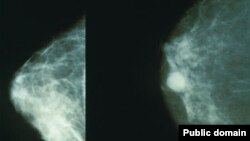

"د سینې سرطان ډېری ناروغانې د خېبر پښتونخوا دي"

ه پاکستان کې څلویښت زره ښځې د سینې سرطان څخه مري او هرو نهه ښځو کې یوه یې د سینې کېنسر ناروغه وي چې ډېری یې د خېبر پښتونخوا او قبایلي سیمو دي.

له مشال راډیو سره په خبرو کې د پينک رېبین ویاند ناصر غفور وویل، هر کال په پاکستان کې څلویښت زره ښځې د سینې سرطان څخه مري او هرو نهه ښځو کې یوه یې د سینې کېنسر ناروغه وي چې ډېری یې د خېبر پښتونخوا او قبایلي سیمو دي.

د پيښور د ارنم هسپتال او د کېنسر ماهره ډاکټر صفورا شاهد وایې چې د سینې کینسر زیاتره کیسونه په هاغه ځوانانو ښځو کې موندل شوي دي چې عمرونه یې د شلو او دیرشو کالونو په منځ کې وي.